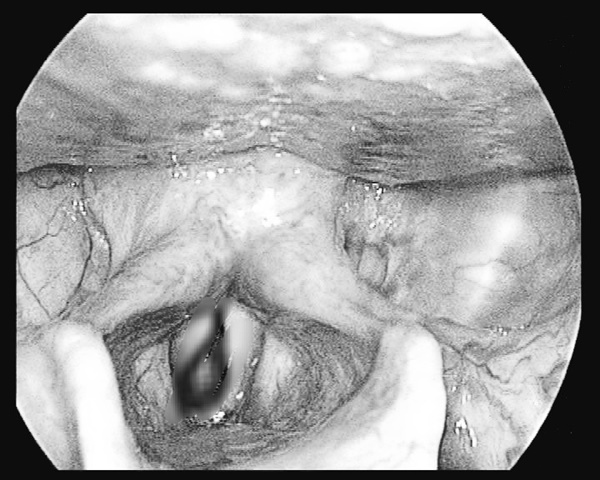

Vào Bệnh viện đa khoa tỉnh Cao Bằng, bệnh nhân được thực hiện các xét nghiệm cận lâm sàng, trong đó có nội soi tai - mũi - họng, các bác sĩ phát hiện trong thanh quản bệnh nhân V. có dị vật là một con đỉa còn sống đang bám vào thanh, khí quản.

Thạc sĩ Bùi Thị Minh Châu, Phụ trách khoa Tai mũi họng, đã phối hợp cùng kíp khoa Gây mê hồi sức tiến hành nội soi gây mê. Trong quá trình nội soi, các bác sĩ gắp ra một con đỉa no máu, dài khoảng 4cm.

Con đỉa dài 4cm sống khỏe trong thanh quản người đàn ông. Ảnh: BVCC

Ngay sau khi gắp được dị vật ra, bệnh nhân đã hết các triệu chứng ngứa ngáy và khó thở, tình trạng sức khoẻ ổn định.